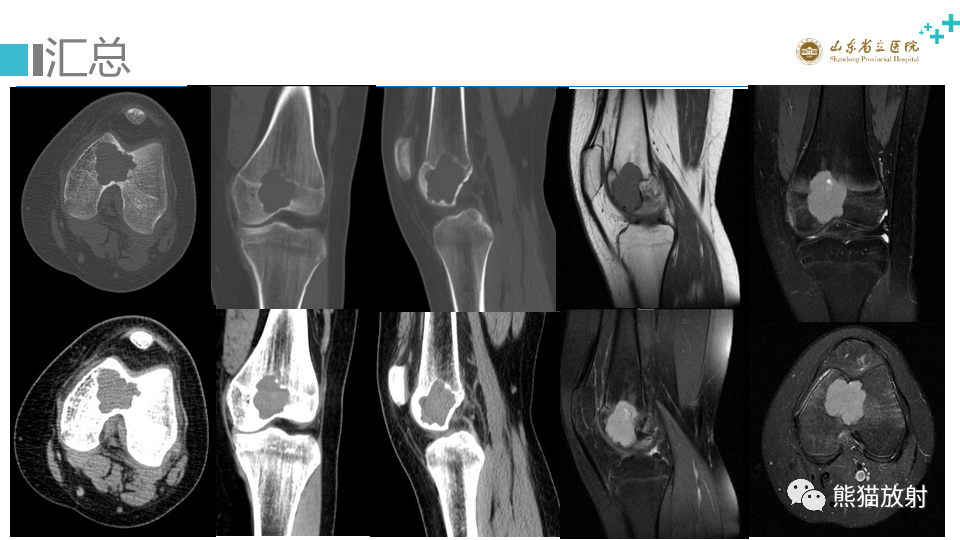

股骨远端动脉瘤样骨囊肿ABC VS 软骨母细胞瘤

【病例】股骨远端动脉瘤样骨囊肿ABC VS 软骨母细胞瘤-5